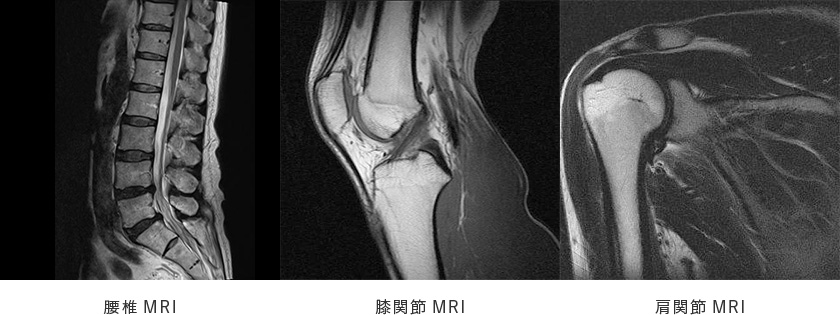

関節や脊椎の変性疾患(変形性股関節症、変形性膝関節症や変形性脊椎症、椎間板ヘルニア、脊柱管狭窄症など)や、骨粗鬆症をはじめ、五十肩、腱鞘炎などの慢性疾患に対して、単純X-P 検査やCT、MRIなどの各種画像診断を用いて適切に診断し、各疾患に対するリハビリテーション(物理療法・運動療法)・内服薬や外用薬の使用、注射による治療(関節腔内注射等)を行っております。

整形外科にてMRI検査が必要と判断された場合、後日予約での対応となる場合がございますので、ご了承ください。